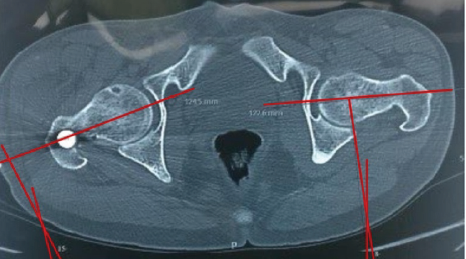

Incidence and Functional Impact of Malrotation after Intramedullary Nailing of Femoral Shaft Fractures: A Prospective Computed Tomography-based Observational Study

Nitish Kumar , Navdeep Singh Keer , Loveneesh G Krishna , Protik Mukherjee , Ishaan Siwach , Balu Ravi